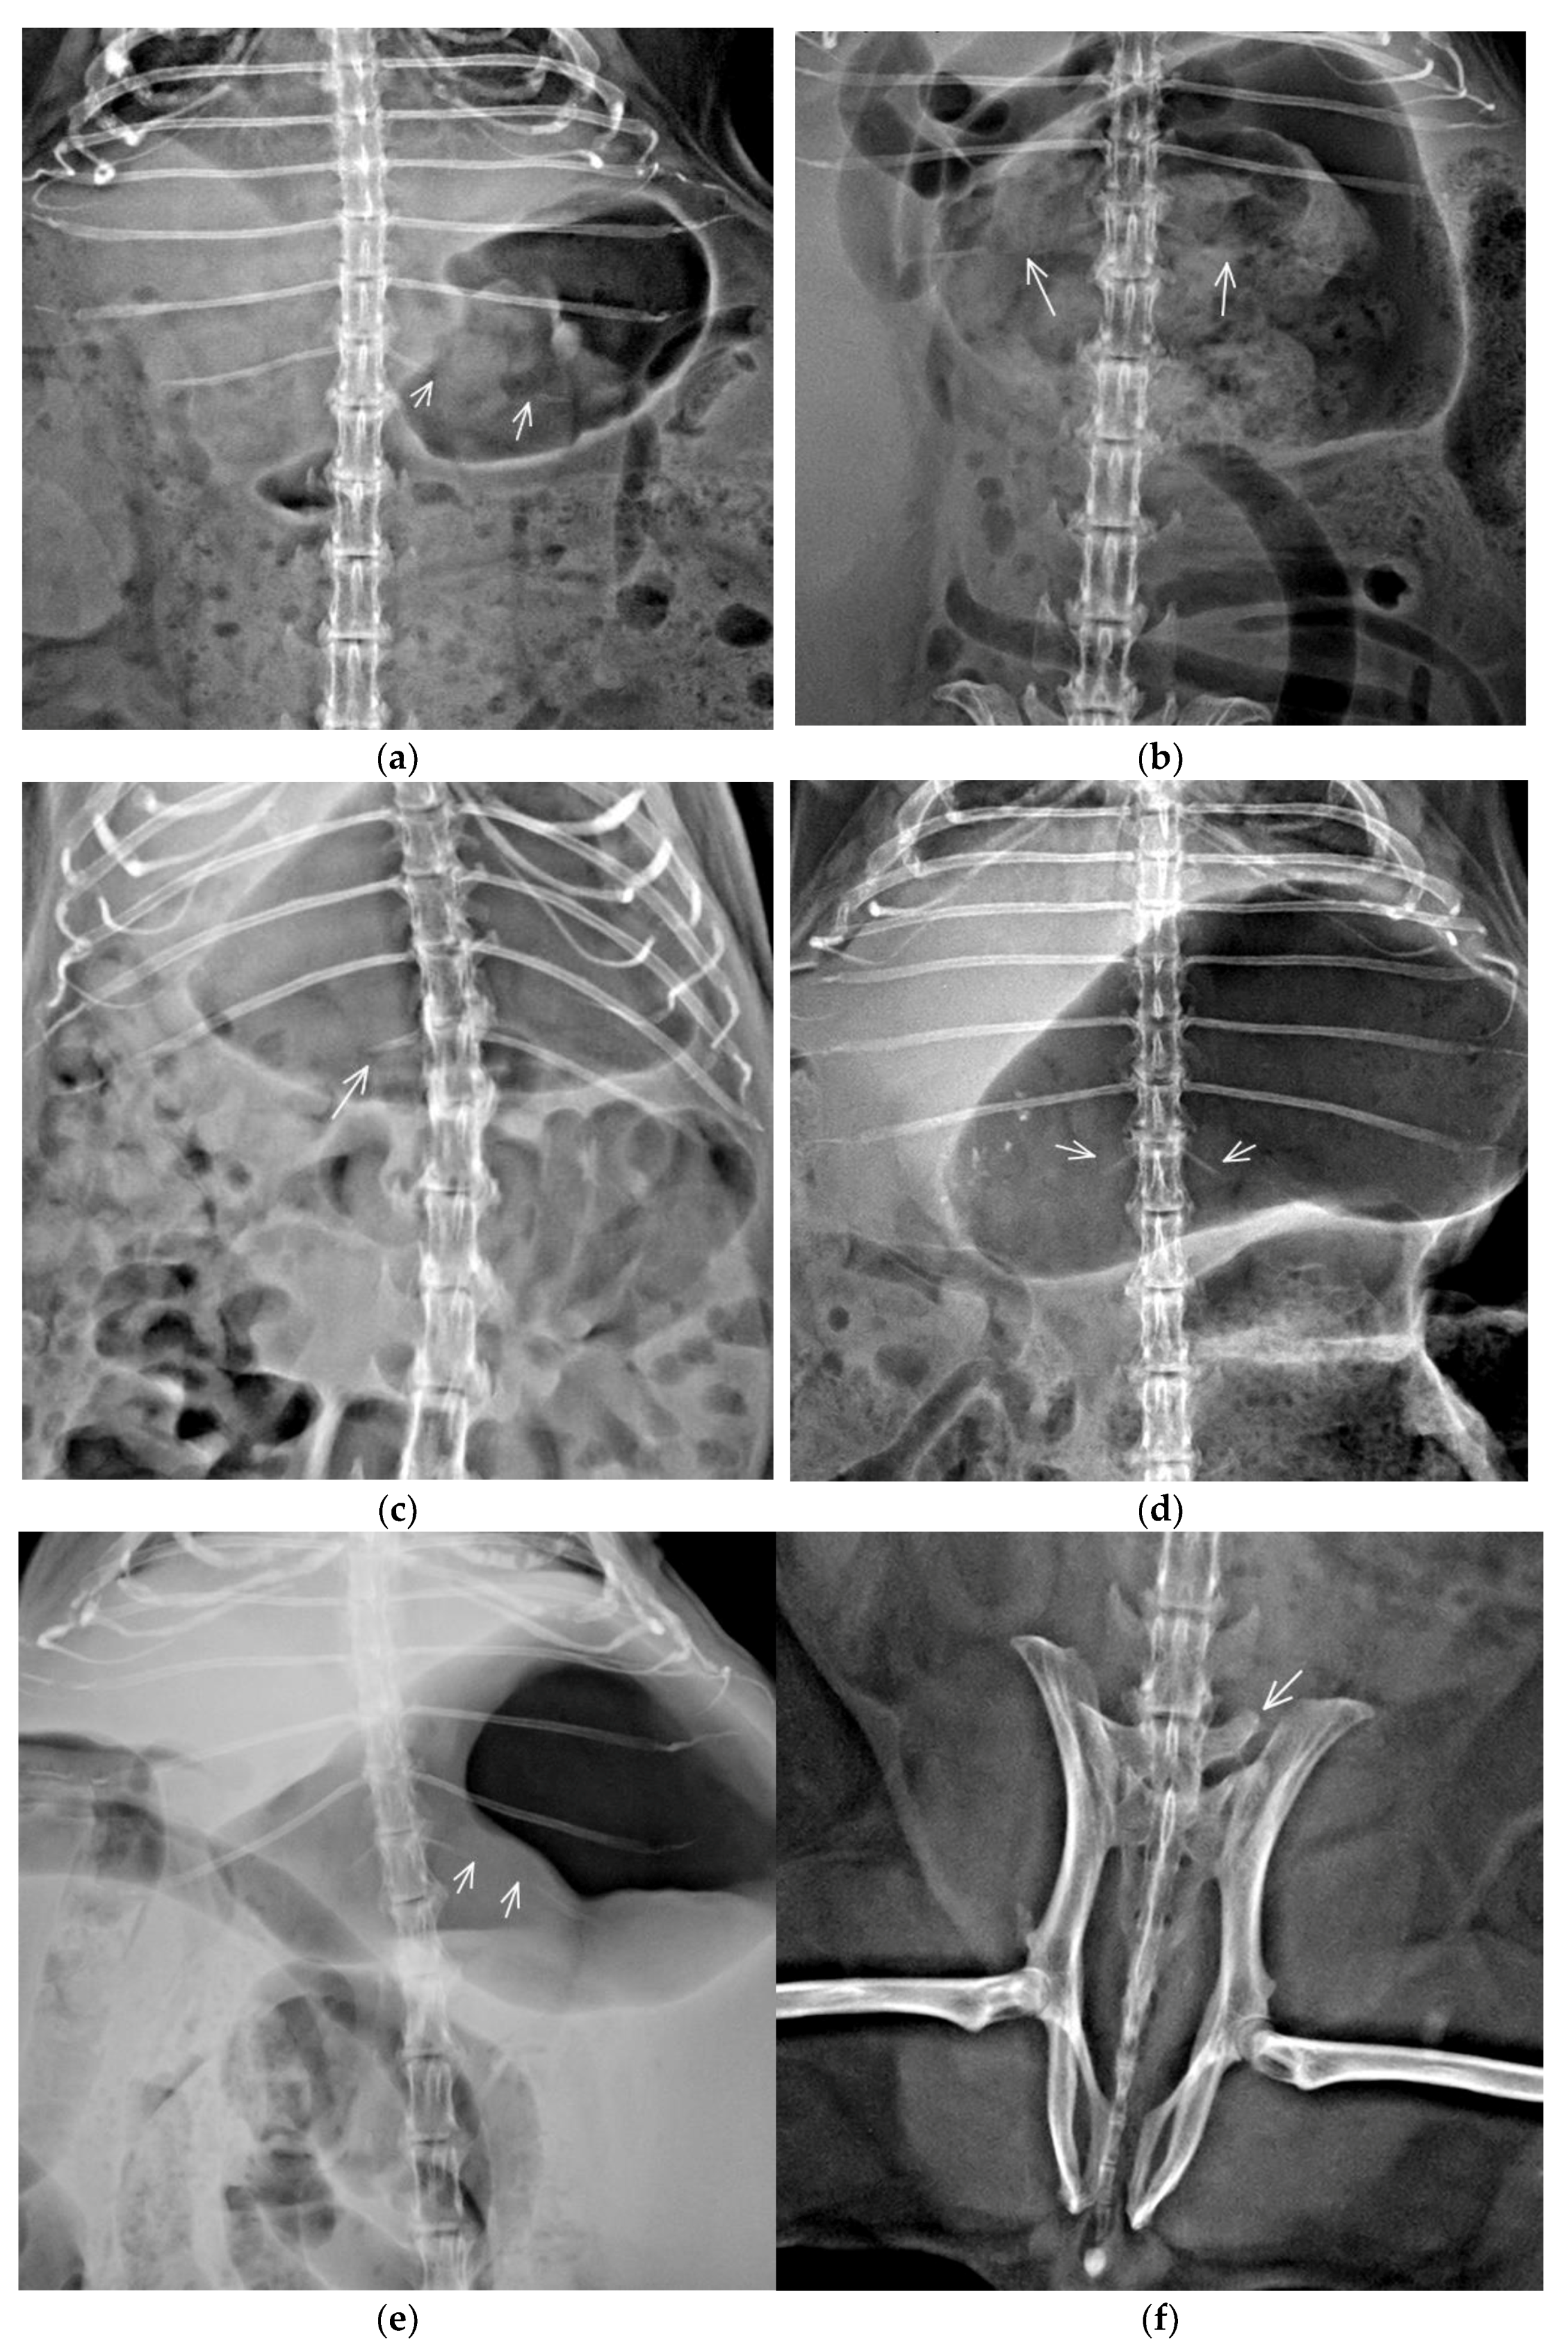

3.2. Congenital Vertebral Anomalies

| TTV | Bilateral incomplete ossification of rib | TL junction | C7/Th13+TTV/L6/S3/Cd7 | 1 | 2.5 | 20 | F |

| TL junction | C7/Th12+TTV/L6/S3/Cd7 | 1 | F | ||||

| TL junction | C7/Th12+TTV/L5/S4/Cd6 | 1 | M | ||||

| TL junction | C7/Th12+TTV/L6/S4/Cd6 | 1 | F | ||||

| TL junction | C7/Th12+TTV/L6/S5/Cd6 | 1 | F | ||||

| TL junction | C7/Th12+TTV/L5/S4/Cd7 | 1 | M | ||||

| Unilateral incomplete ossification of rib | TL junction | C7/Th12+TTV/L5/S4/Cd7 | 2 | 3.33 | 26.67 | F | |

| TL junction | C7/Th12+TTV/L6/S4/Cd6 | 1 | M | ||||

| TL junction | C7/Th12+TTV/L5/S4/Cd6 | 1 | F | ||||

| TL junction | C7/Th12+TTV/L6/S4/Cd7 | 1 | F | ||||

| TL junction | C7/Th13+TTV/L5/S4/Cd6 | 1 | F | ||||

| Bilateral rudimentary rib | TL junction | C7/Th12+TTV/L5/S4/Cd7 | 1 | 1.25 | 10 | F | |

| Unilateral rudimentary rib | TL junction | C7/Th12+TTV/L6/S3/Cd7 | 1 | 1.67 | 13.33 | F | |

| TL junction | C7/Th12+TTV/L6/S4/Cd5 | 1 | M | ||||

| Unilateral rudimentary rib and contralateral incomplete ossification of rib | TL junction | C7/Th12+TTV/L6/S4/Cd6 | 1 | 0.42 | 3.33 | F | |